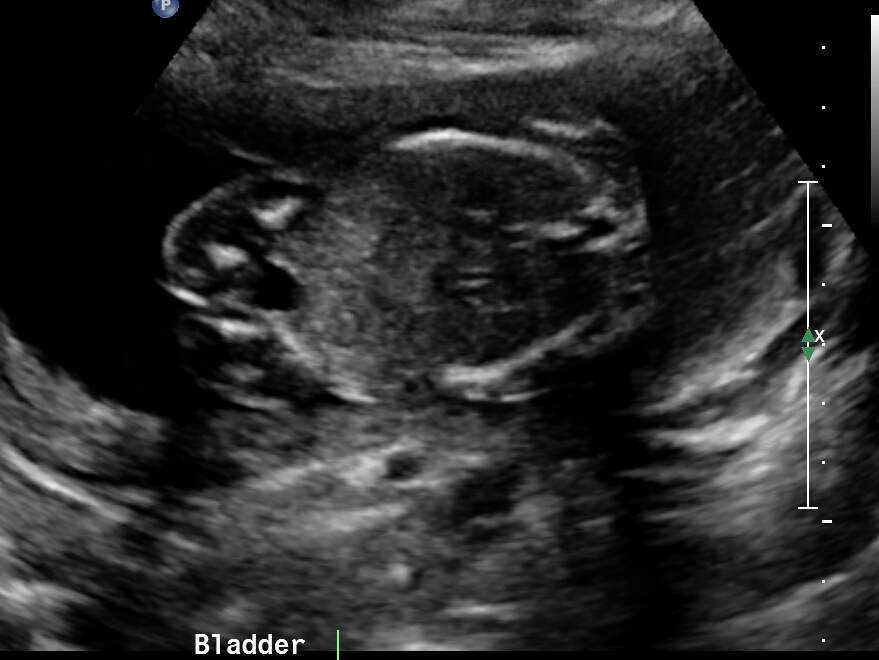

Just wondering if any gender clues can be seen in these pics? Attachment 37755Attachment 37756Attachment 37757